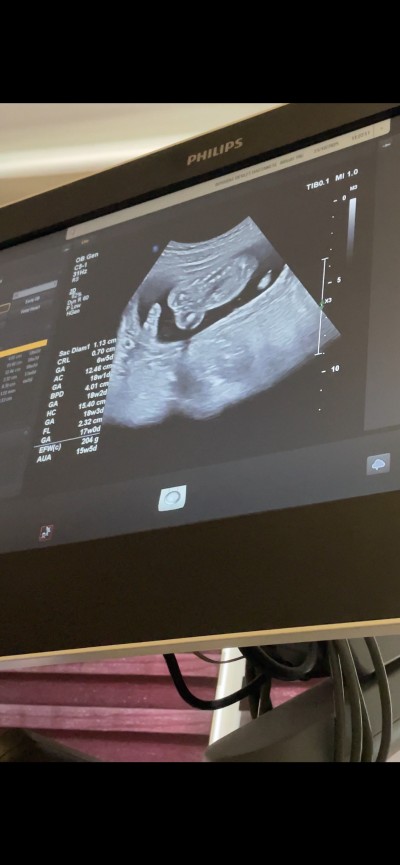

3 çizgi olunca kız oluyor benimki kız mesela ama doktor dediği gibi erkek Seninde bide 16 haftasın belli yani Bak benim

image ultoroson kız üç çizgi

Ben 15 te gittim erkek dedi bi doktor çıkıntı var dedi sonra 15+4 de perinatolojiye gittim kız dedi 18 de bida gittim kız dedi 22 de gene gittim kız dedi kız nasıl anlatayım bizde varya vajina o işte ultorosonda 3 çizgi gibi durur

Erkek bebekte penis ve yumurtalık olur ya normalde kızdada üç çizgi var testisleri yok  kız dedi bana